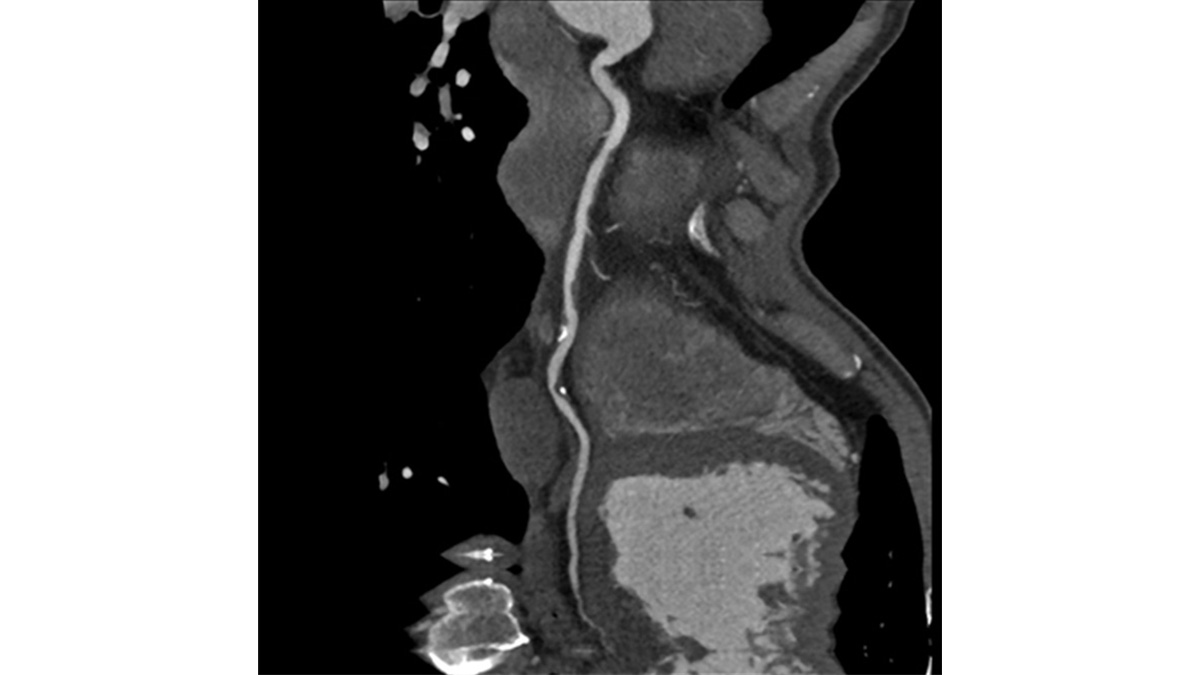

BILDGEBUNG VON HERZEN UND GEFÄSSEN

Herz und Gefäßerkrankungen werden bei der Computertomographie sichtbar

Herz- und Gefäßerkrankungen sind in Deutschland extrem häufig und sind zunehmende Domäne der Schnittbildgebung in CT und MRT. In der Computertomographie verfügt das Institut über ein Canon Aquilion ONE Prism als Volumenscanner, der mit einer Umdrehung einen kompletten Herz-Scan fahren kann. Gegenüber konventionellen CT-Scannern ist eine Coronar-CT-Untersuchung bis zu einem Kalk-Score (Agatston-Score) von 2960 möglich. Mit dem PIQE-Algorithmus ist eine gestochen scharfe Abbildung des Gefäßlumens möglich. Darüber hinaus ist eine dynamische Myokardperfusion ähnlich zur MRT jetzt mithilfe der Spektralanalyse auch in der Computertomographie an diesem Gerät möglich geworden. In der Kernspintomographie steht ein MRT 1.5 Tesla Achieva dStream 1.5T Nova Dual der Firma Philips zur Verfügung. Hier ist die kardiologische Untersuchung in hoher örtlicher Auflösung (cardiac-zoom) und hoher zeitlicher Auflösung (k-t SENSE) möglich. Untersuchungen in freier Atmung sind ebenfalls möglich geworden. T1 und T2 Mapping gehören selbstverständlich zum Untersuchungsumfang mit dazu.